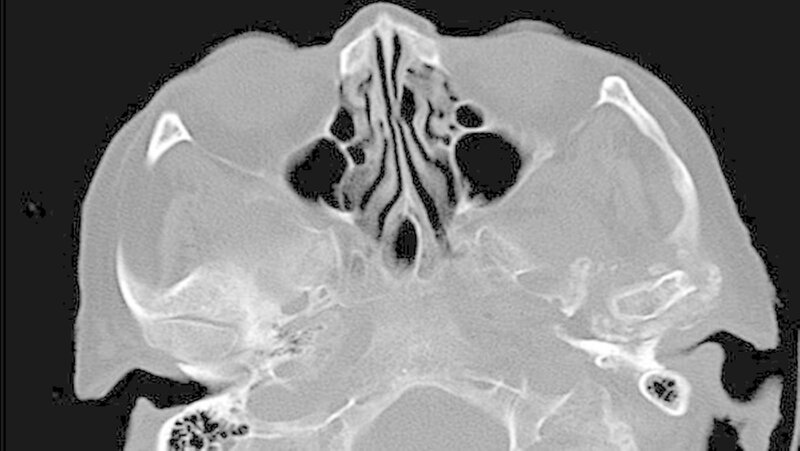

Die klinische Untersuchung zeigte eine überwärmte, schmerzhafte Schwellung präauriculär links und eine stark eingeschränkte Mundöffnung bei zahnlosem Kiefer. Das angefertigte Orthopantomogramm und die Schädelaufnahme in posterior-anteriorer Projektion gaben keinen eindeutigen Hinweis auf Pathologien im Bereich des linken Kiefergelenks, mit denen die ausgeprägten Beschwerden der Patientin hätten erklärt werden können.

Es war lediglich ein stark verschmälerter Gelenkspalt im Bereich des linken Kiefergelenks erkennbar, woraufhin eine Computertomografie des Unterkiefers durchgeführt wurde (Abbildungen 1 und 2). Dabei zeigten sich eine Deformierung des linken Kiefergelenksköpfchens mit Unregelmäßigkeiten der Kortikalis sowie eine Fremdkörpereinlagerung (freie Gelenkkörperchen) im Bereich des Gelenkspalts (Abbildungen 3 und 4).